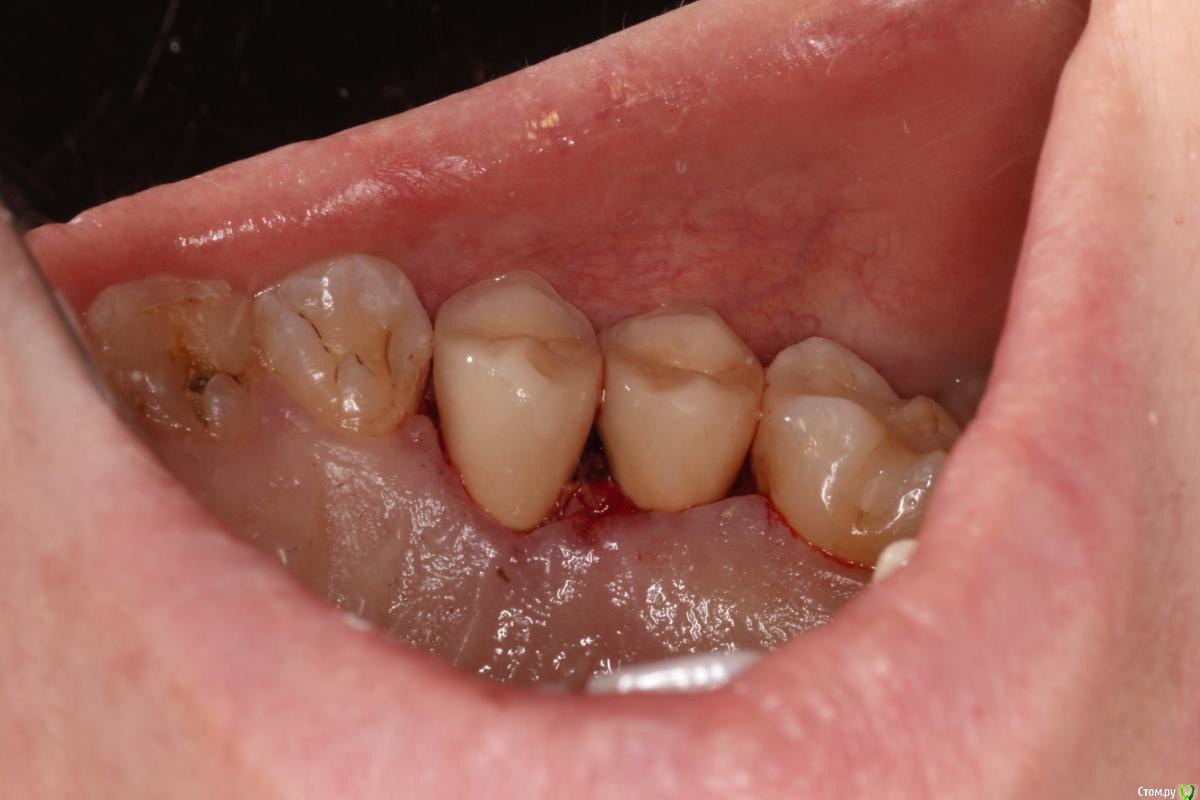

skeettrap Опубликовано 5 июля, 2016 Поделиться Опубликовано 5 июля, 2016 Стандартная ситуация : коллега попросила сделать родственнице (мужа) за неделю - во время краткосрочного визита из Израиля.Исходная ситуация 14,15 сильно разрушены с временными пломбами и наплывшей десной(фото не сделал).На первом этапе сделаны культевые вкладки прямым методом (десну подрезал бором). Постановка вкладок на следующий день, изготовление временных коронок, снятие слепков. Через 2 дня - фиксация. Ссылка на комментарий

skeettrap Опубликовано 6 июля, 2016 Автор Поделиться Опубликовано 6 июля, 2016 На удлинение времени не было. Главное было проснять. Временные делаю так: после замешивания немного жду, когда начинает полимеризоваться, делаю типа брусочка, даю накусить, немного с боков приминаем (это при открытом рте). До окончательного отверждения несколько раз вынимаю и вставляю. По мере нагрева помещаю в холодную воду.После отверждения формирую предварительно, внутри немного убираю и делаю перебазировку. Окончательно формирую и фиксирую. Ссылка на комментарий